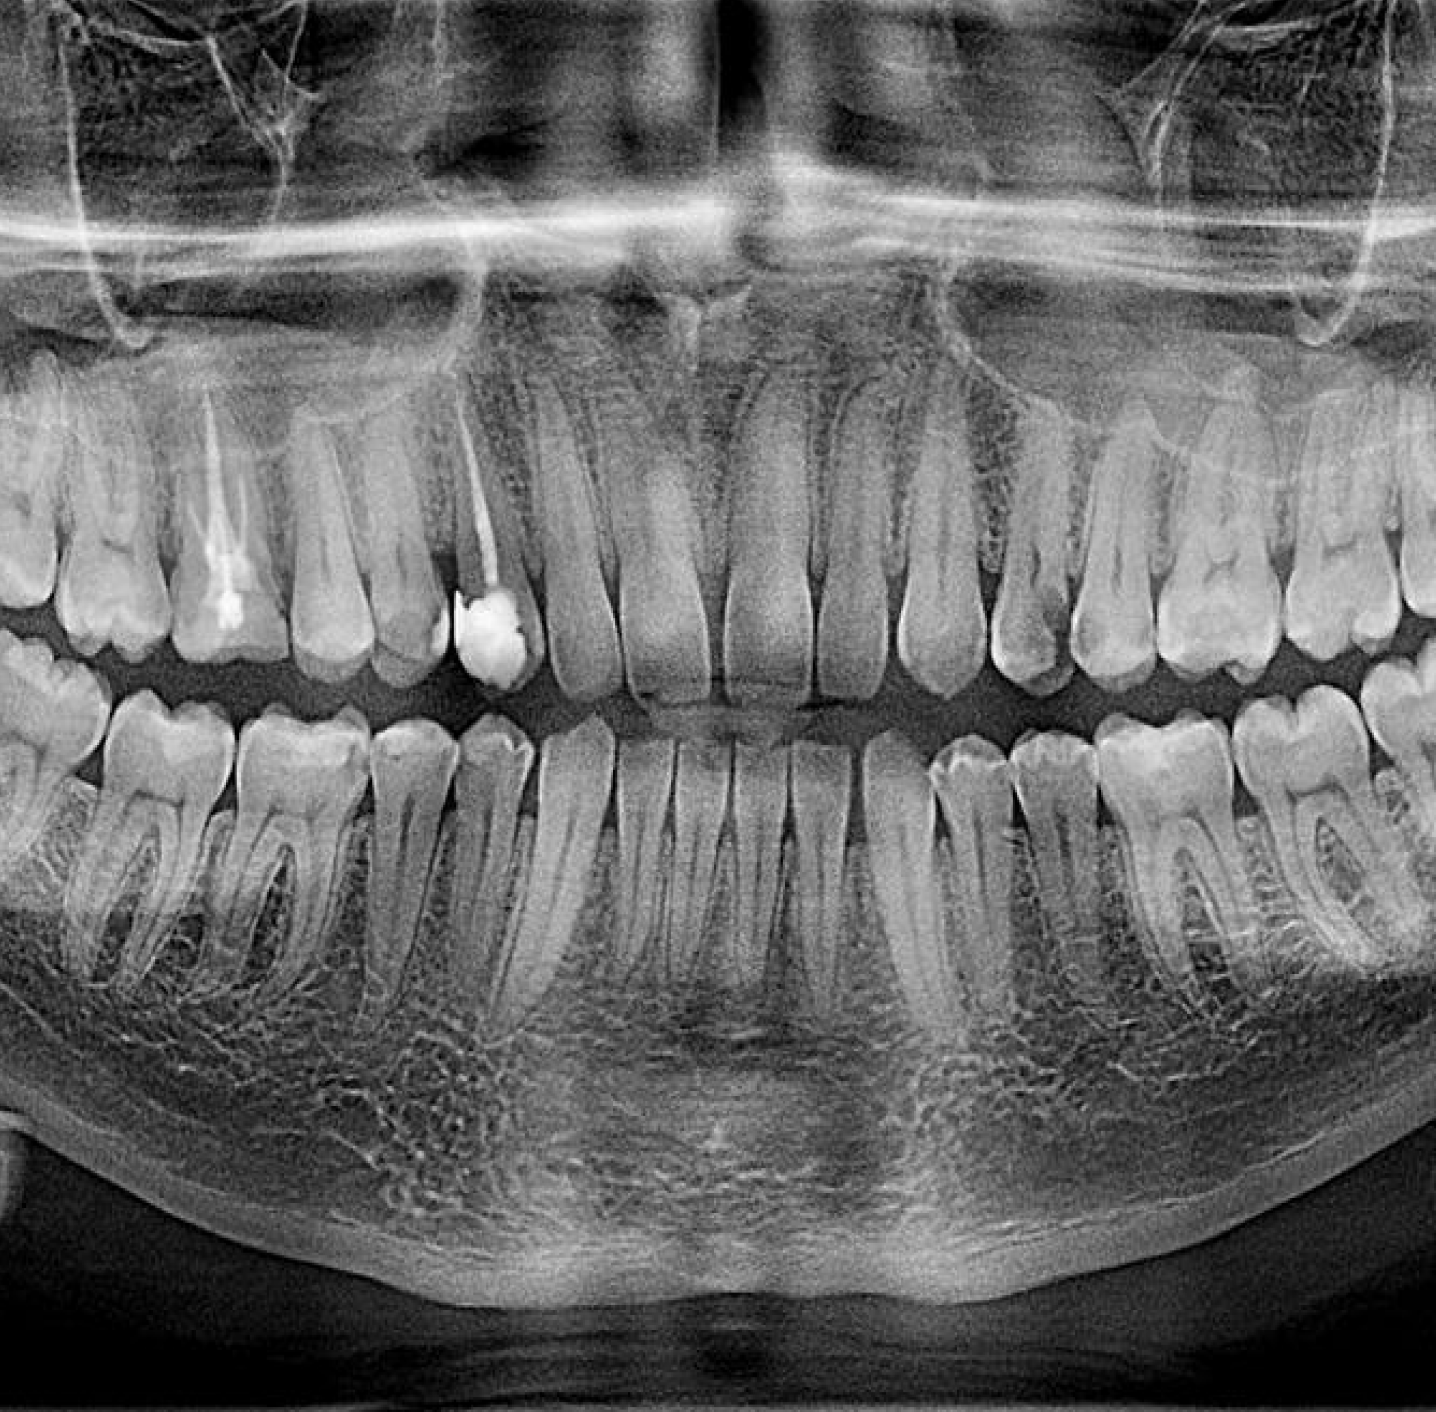

Панорамний знімок

Це загальний рентген-знімок зубів верхньої та нижньої щелепи, що представляє картину в одній площині і є базовим "діагностичним мінімумом".